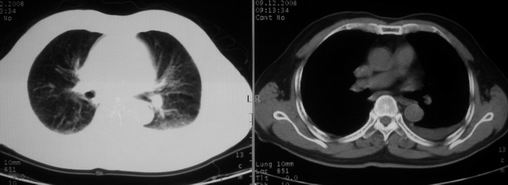

男,78岁,咳嗽、咳痰、发热入院,抗炎治疗一周后已退热,咳血似痰。

10月9日片:

两肺炎症感染(以左肺下叶为著),双侧少量胸腔积液;建议继续抗炎治疗。